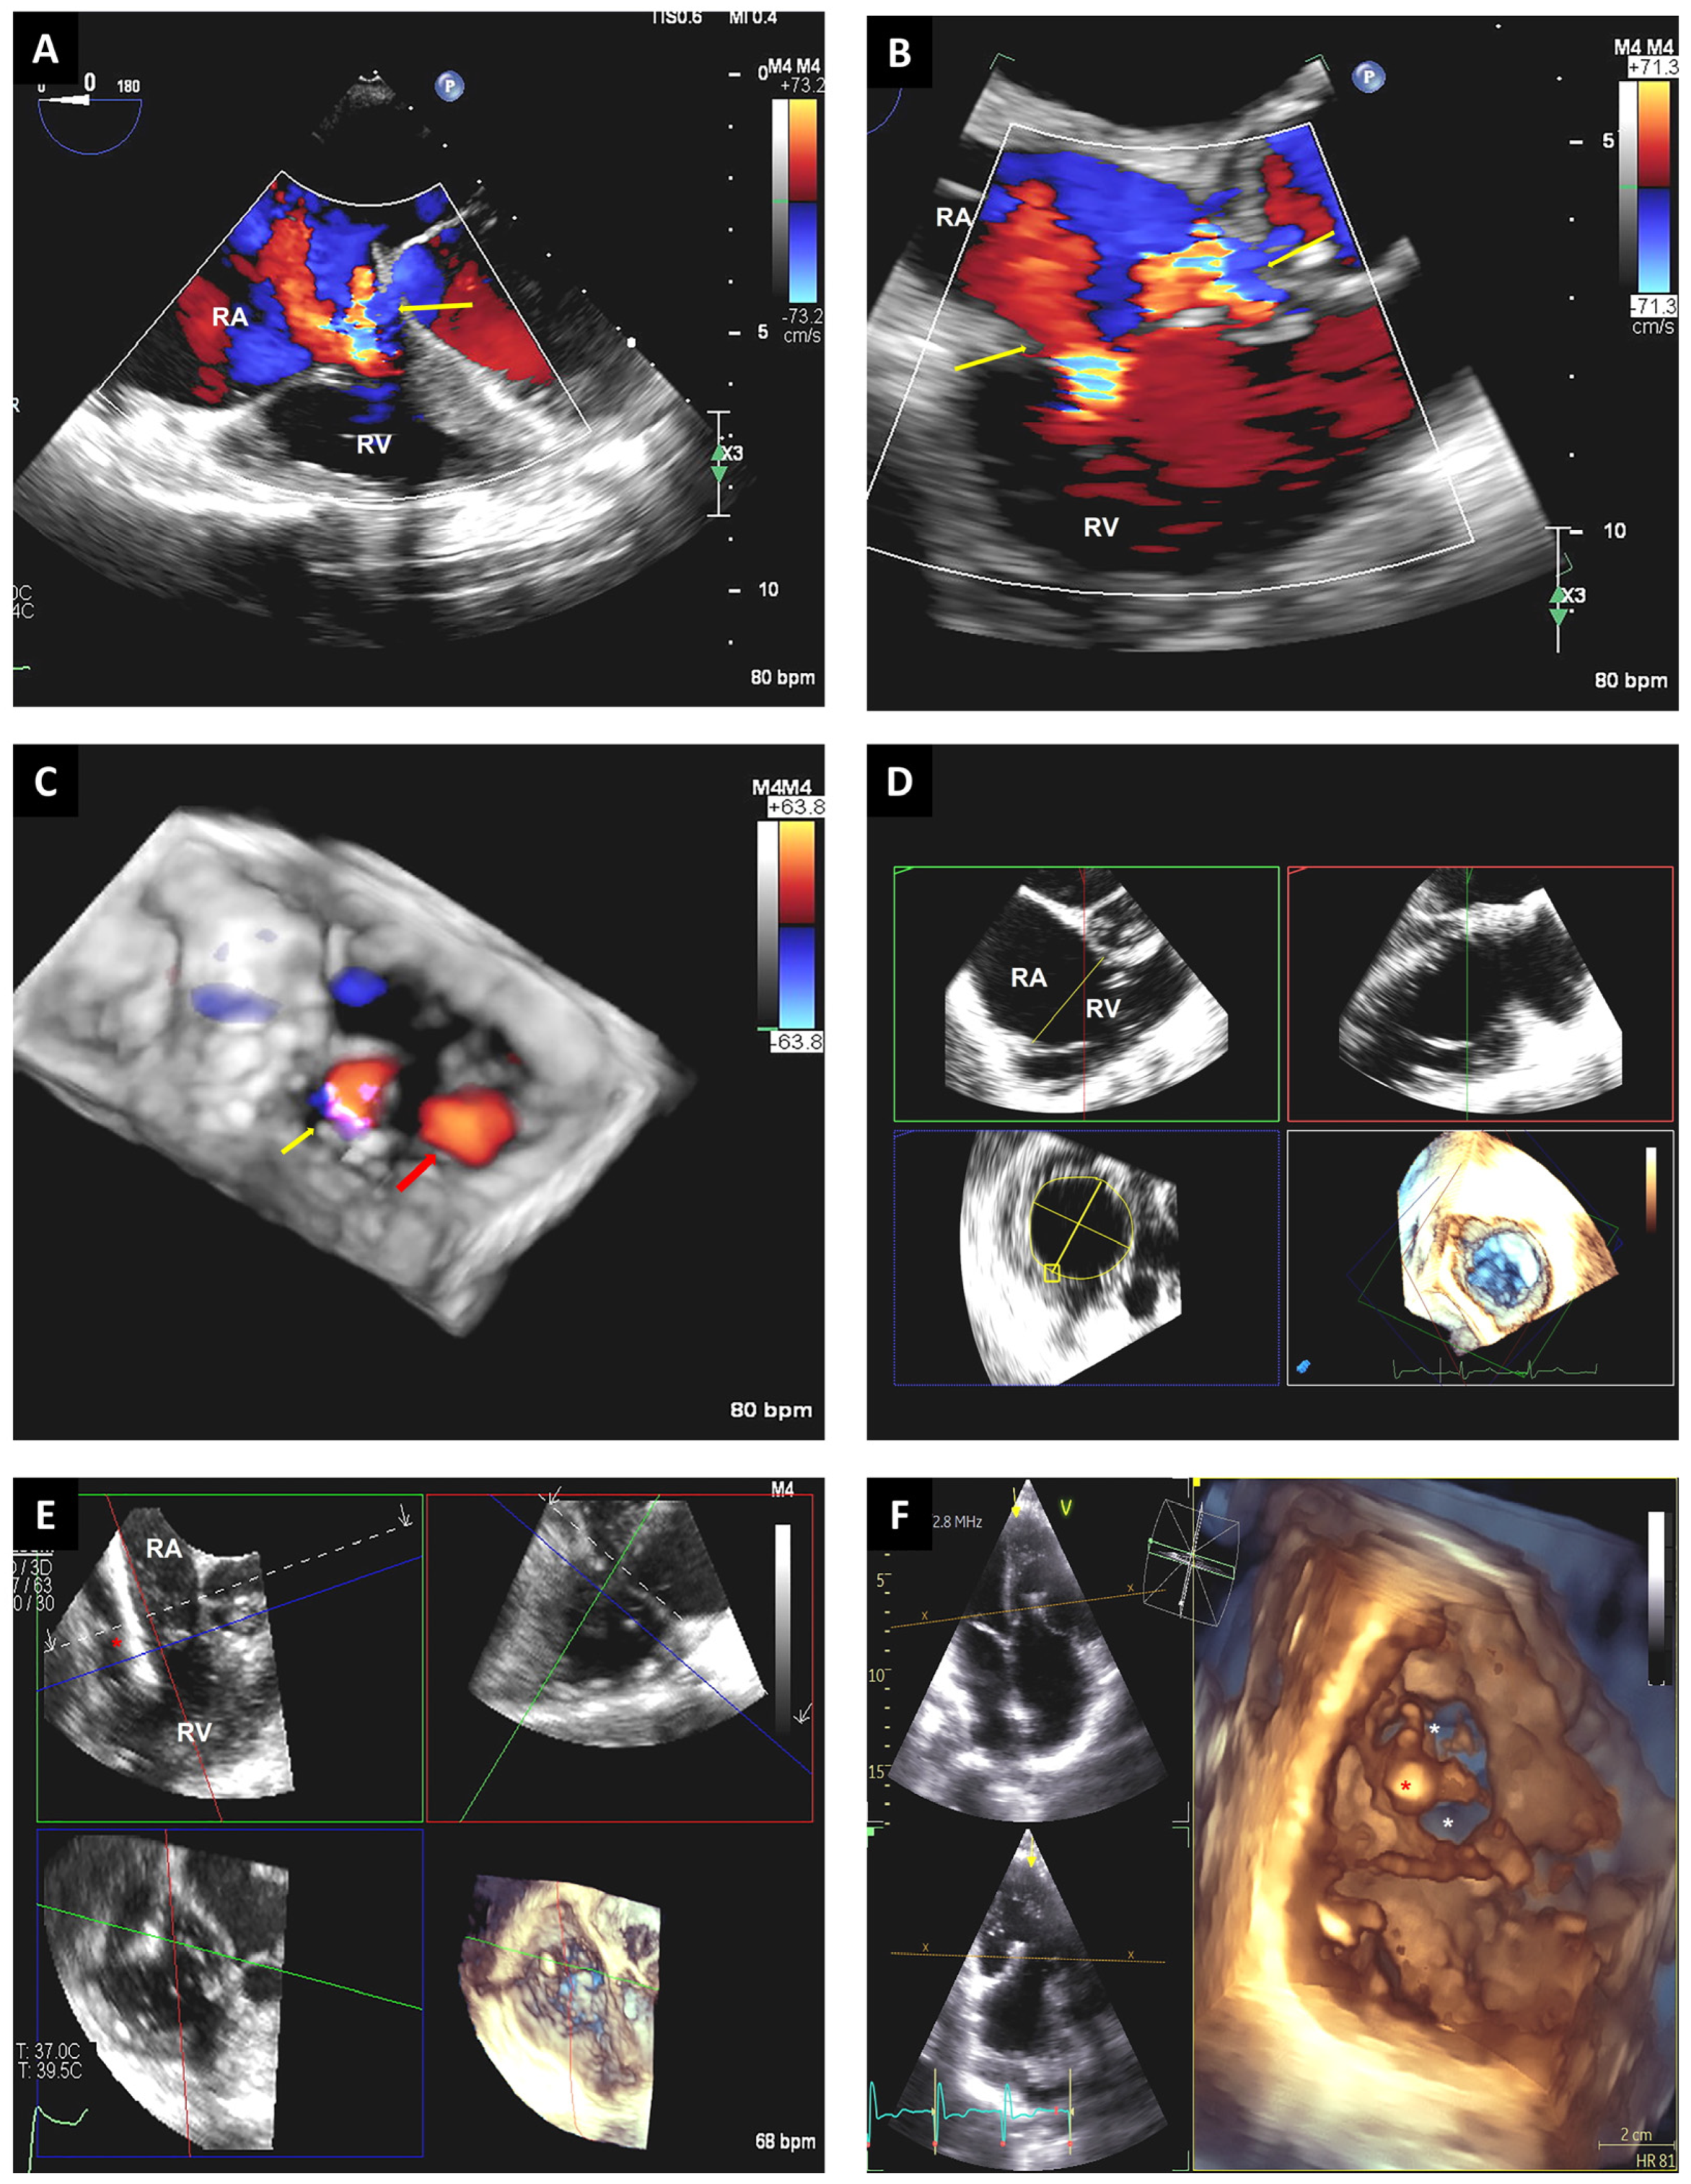

3.4. Tricuspid Valve Interventions

3.5. Left Atrial Appendage Closure